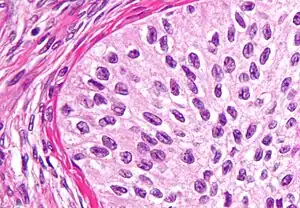

| High magnification micrograph of a Brenner tumor, a type of surface epithelial-stromal tumor. H&E stain. | |

Brenner tumors are uncommon surface-epithelial stromal cell tumors in which the epithelial cell (which defines these tumors) is a transitional cell. These are similar in appearance to bladder epithelia. The tumors may be very small to very large, and may be solid or cystic. Histologically, the tumor consists of nests of the aforementioned transitional cells within surrounding tissue that resembles normal ovary. Brenner tumors may be benign or malignant, depending on whether the tumor cells invade the surrounding tissue.